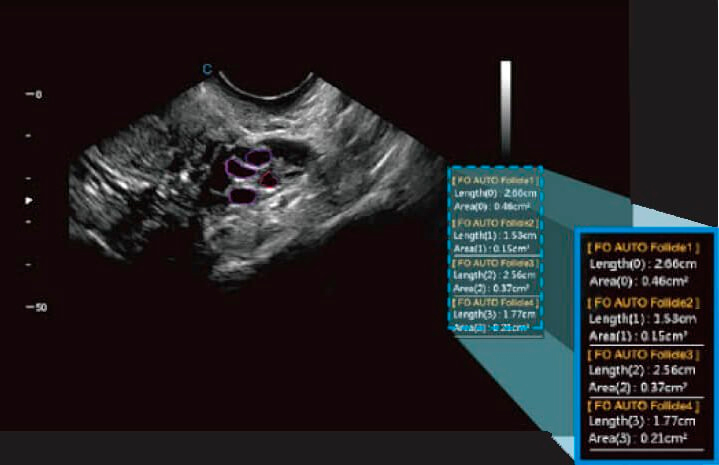

Détection automatique des follicules

- Quantifier le nombre de follicules et indiquer leur taille individuelle.

- Il devient un outil qui facilite la fluidité au travail.

- Parvient à guider le professionnel vers le traitement le plus précis et le plus précis.